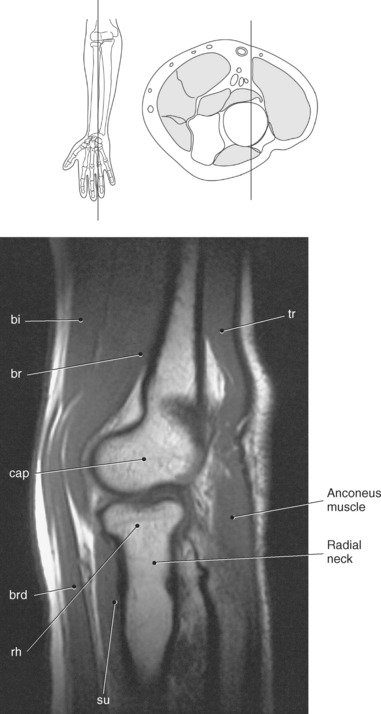

Figure 9.71 Coronal T1-weighted MR scan of elbow.

Key: ol, Olecranon fossa; me, medial epicondyle; tro, trochlea; le, lateral epicondyle; cap, capitellum; rh, radial head; rt, radial tuberosity; rn, radial notch; corn, coronoid process.

Figure 9.74 Sagittal, T1-weighted MR scan of elbow with proximal radius.

Key: bi, Biceps; br, brachialis; cap, capitellum; brd, brachioradialis; rh, radial head; su, supinator; tr, triceps; ol, olecranon fossa; tro, trochlea; corn, coronoid process; le, lateral epicondyle; u, ulna; me, medial epicondyle.